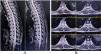

Case 6: acute longitudinally extensive transverse myelitisA 36-year-old previously healthy man presented to the emergency department with acute onset paresthesias below mid-chest level, urinary retention, and weakness of lower limbs for the last two days. Urinary retention was relieved by Foley catheterization. He complained of intermittent lancinating/sharp-shooting pain involving his lower limbs and altered perception of hot and cold below the mid chest level. He also complained of a high-grade fever associated with headache and body ache for the last 12 days, which did not subside with some local remedies from an indigenous medical practitioner. On examination, he was febrile with relative bradycardia. Neurological examination was compatible with dorsal transverse myelopathy.

Complete blood cell count was noteworthy for anemia (hemoglobin 10.9 g/dL), neutrophilic leukocytosis (16 300/µL; 76% neutrophils), and raised erythrocyte sedimentation rate (62 mm in the first hour). Serologies for malaria, dengue, Japanese encephalitis, borreliosis, typhoid fever, hepatitis A, B, C, E, and HIV (1, 2) were negative. Contrast-enhanced MRI of the spinal cord revealed a high signal intensity lesion and swelling extending from the D4–D5 level to the distal cord region (Fig. 4). CSF examination showed high protein (97 mg/dL), normal glucose (45 mg/dL) and lymphocytic pleocytosis (19 cells; all lymphocytes). Serology for tsutsugamushi infection (IgM-ELISA and Immunofluorescence antibody) was positive. Anti-aquaporin 4-antibodies, anti-myelin oligodendrocyte glycoprotein antibodies, serologies for neuroviruses, neurotuberculosis, and neurosarcoidosis were tested negative. Based on the MRI findings and Orientia tsutsugamushi titers, acute longitudinally extensive transverse myelitis following scrub typhus was the most tentative diagnosis. Intravenous doxycycline (200 mg/day) for 14 days and high-dose pulse intravenous methylprednisolone therapy (1 g/day) for five days was administered. Following steroidal therapy, leg weakness improved gradually to an mMRC grade 4+ within the next two weeks, and urinary control improved. He was discharged after four weeks from the hospital with minimal neurological deficits. Follow-up MRI at 12 months was normal. At one-year follow-up, the patient could walk without assistance.

Case 6: only five cases with acute transverse myelitis have been reported.45–49 Longitudinally extensive transverse myelitis (LETM) is defined as a spinal cord lesion that extends over three or more vertebral segments on MRI.50–52 Affecting more than two-thirds of spinal cord thickness from the center, LETM typically involves a dramatic presentation consisting of paraparesis or quadriparesis, sensory disturbances, and bladder, bowel and/or sexual dysfunction.50–52 Although it is a characteristic of neuromyelitis optica, similar spinal lesions can also occur in various diseases involving the central nervous system, e.g., sarcoidosis, Sjögren syndrome, multiple sclerosis, neoplasms, or traumatic spinal cord injury, among others.50–52 Borrelia, Chlamydia, cytomegalovirus, mumps virus, Coxsackie virus, Mycobacterium tuberculosis, Mycoplasma, enterovirus 71, hepatitis C virus, Brucella, Ascaris, Toxocara, and Schistosoma are also known to be associated with LETM.50–52 In our patient, after excluding all the common etiologies of LETM, we were left with para-infectious LETM following tsutsugamushi infection. In the previously reported similar cases of scrub typhus-induced para-infectious LETM, the onset of symptoms ranged from four to 14 days after the onset of fever.45–49 MRI variably showed predominantly grey-matter myelitis involving cervical, dorsal and lumbar cord enhancement and swelling.45–49 All patients were managed with steroids in conjunction with doxycycline, which favors an immunological basis underlying this presentation in scrub typhus.45–49 Scrub typhus should be kept as a differential diagnosis in patients with acute undifferentiated fever and LETM in endemic areas.